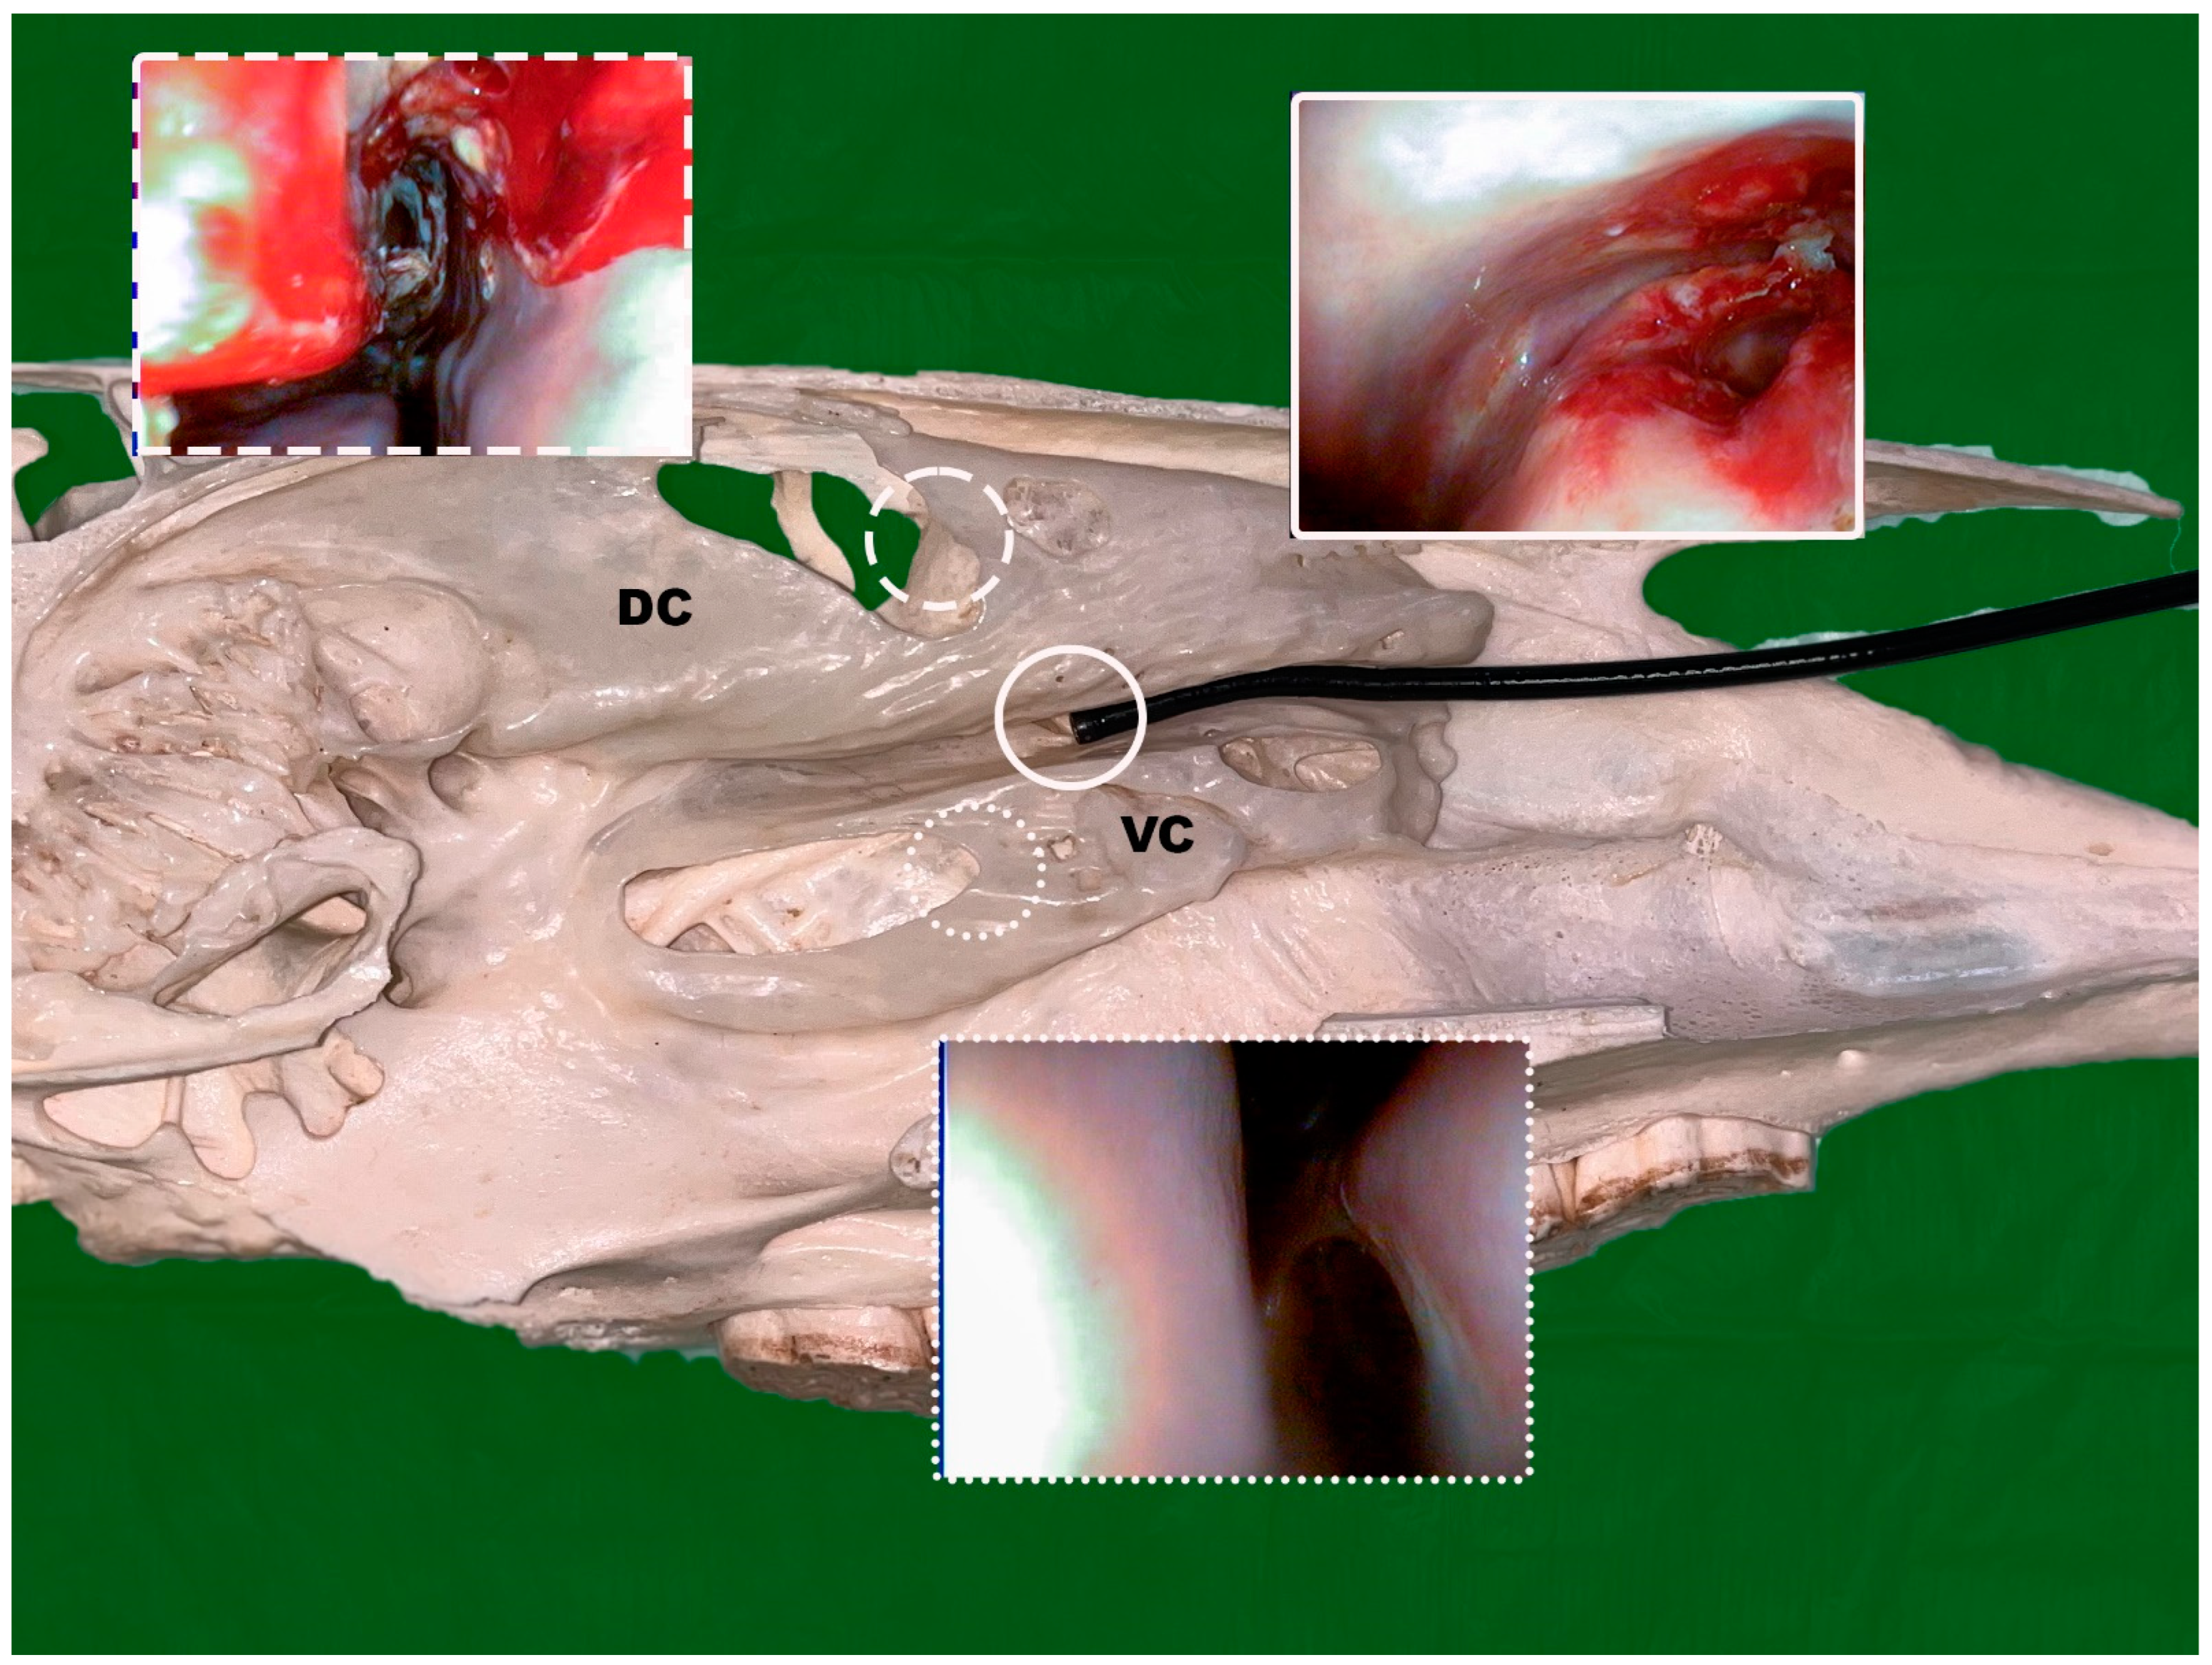

2.2.1. Transnasal Sinus Endoscopy (TNSE)

2.2.3. Widening of the Nasomaxillary Opening/Channel Using a Foley Catheter

2.2.4. Endoscopic Guided Conchotomy

2.2.5. Transendoscopic Laser Fenestration of the Nasal Conchae

2.2.6. Transendoscopic Fenestration of the Bulla of the Maxillary Septum (BMS)

3.1.1. TNSE

3.1.2. Balloon Sinuplasty

3.1.3. Conchotomy and Transendoscopic Laser Fenestration of the Bulla of the Maxillary Septum